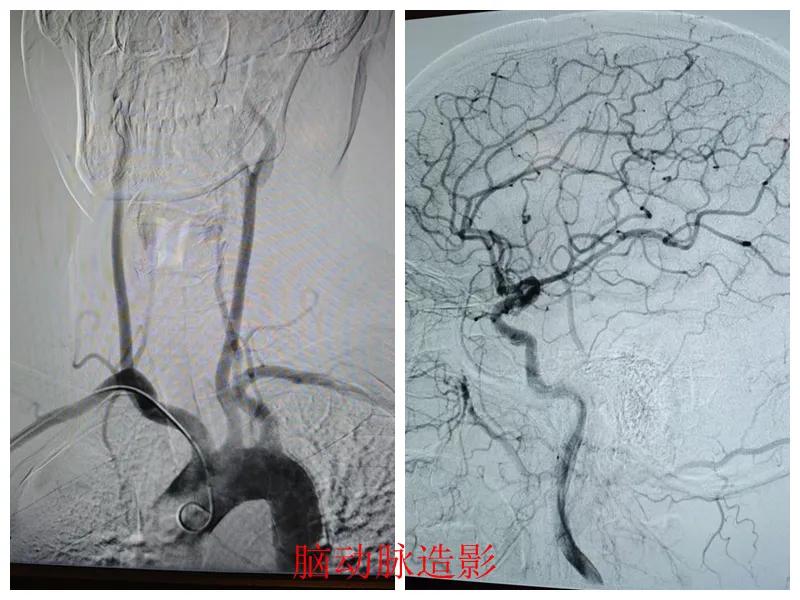

心腦聯(lián)防 腦心同治——市二院開(kāi)展常態(tài)化心腦聯(lián)合造影

近日,市二院心血管內(nèi)科聯(lián)合介入科為患者成功實(shí)施了“心腦同治”聯(lián)合造影手術(shù),標(biāo)志著醫(yī)院在“心腦同治”介入治療方面取得了顯著進(jìn)展,為同時(shí)合并心腦血管疾病的患者查清了病癥,取得了良好的診療效果。

患者張某,47歲,因胸悶、左上肢麻木20天到市二院心血管內(nèi)科就診,結(jié)合既往冠脈CTA、頭頸聯(lián)合CTA結(jié)果、高血壓病史以及入院后的輔助檢查結(jié)果,診斷為冠狀動(dòng)脈重度狹窄、頸動(dòng)脈狹窄。

經(jīng)王瑾院長(zhǎng)和心血管內(nèi)科、介入科多學(xué)科專家會(huì)診后,決定為患者進(jìn)行冠狀動(dòng)脈和腦血管聯(lián)合造影檢查,一次性完成心腦血管評(píng)估,并同步開(kāi)展腦血管及冠心病介入治療。

術(shù)前準(zhǔn)備完善后,在王瑾院長(zhǎng)帶領(lǐng)下,心血管內(nèi)科主任李慧新、影像科主任宋貴良、副主任醫(yī)師趙進(jìn)科等緊密協(xié)作,成功為患者實(shí)施了冠狀動(dòng)脈造影及腦動(dòng)脈造影兩項(xiàng)檢查。冠狀動(dòng)脈造影結(jié)果提示:患者右冠狀動(dòng)脈慢性閉塞,腦動(dòng)脈造影提示腦血管多支狹窄病變。

術(shù)后,根據(jù)造影檢查結(jié)果,科室團(tuán)隊(duì)為患者制定了個(gè)體化的治療方案,經(jīng)過(guò)一段時(shí)間的規(guī)范化治療,患者很快便康復(fù)出院。